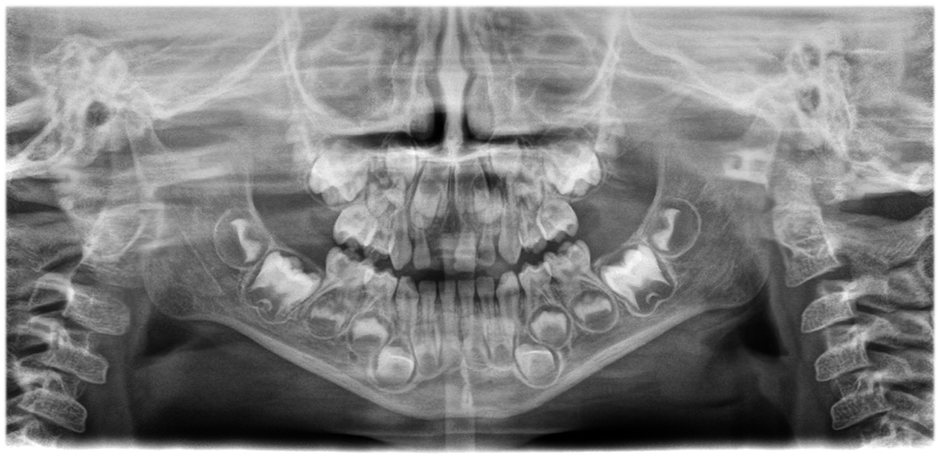

• Images panoramiques d'une clarté et d'une définition exceptionnelles

avec le système innovant d'autofocus à 21 couches intégré de manière transparente à une correction du positionnement du patient.

Déplacez le curseur pour voir la différence (image de gauche sans, image de droite avec autofocus et correction de la position du patient)